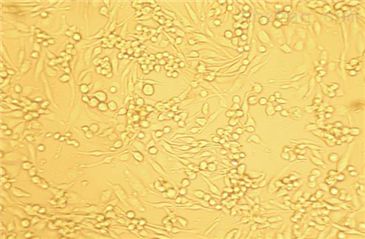

我司HS776T(人胰腺癌细胞)是细胞专业的供应商,竭力为您提供的产品和售后服务,保障您科研工作的顺利进行,欢迎您询价订购。

HS776T(人胰腺癌细胞)